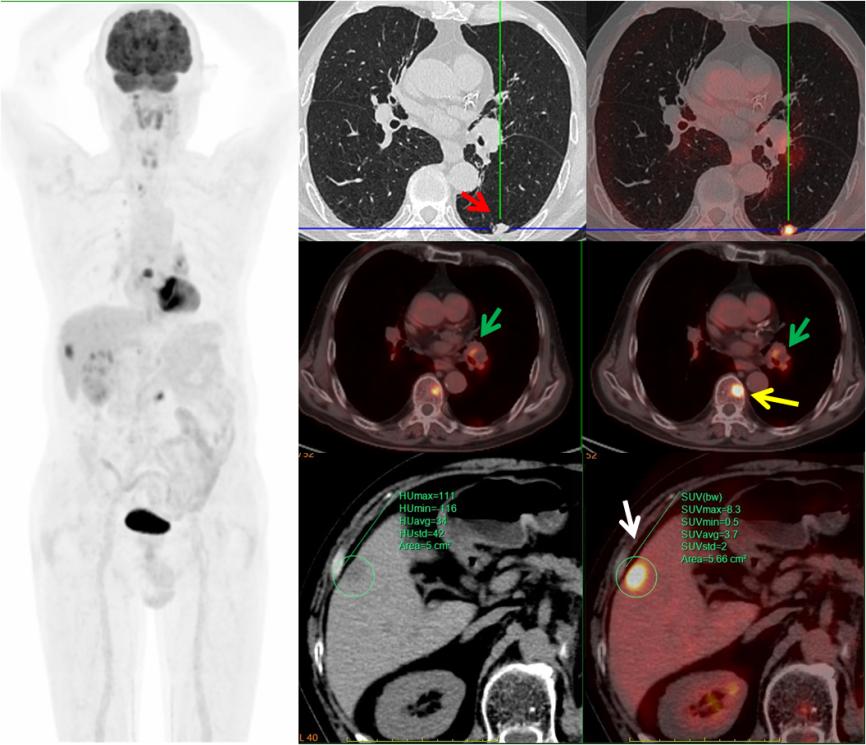

病例3,中年男性,左腎癌術(shù)后三個(gè)月,PET/CT示左肺下葉(紅箭)、左肺門淋巴結(jié)(綠箭)、肝臟(白箭)、多發(fā)椎體(黃箭)高代謝灶,考慮左肺下葉原發(fā)MT可能,病理證實(shí)為小細(xì)胞神經(jīng)內(nèi)分泌癌。